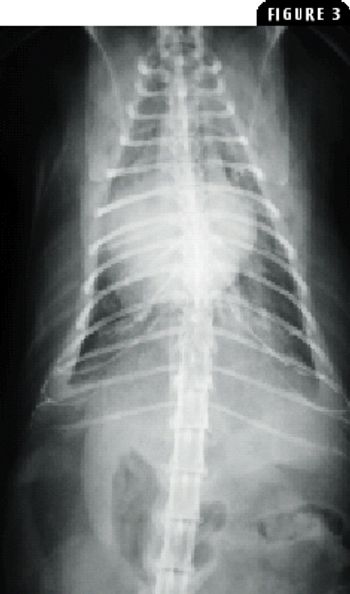

A 10-year-old 35.9-lb (16.3-kg) intact female Wheaton terrier was referred to the teaching hospital at Virginia Tech for evaluation of dyspnea.